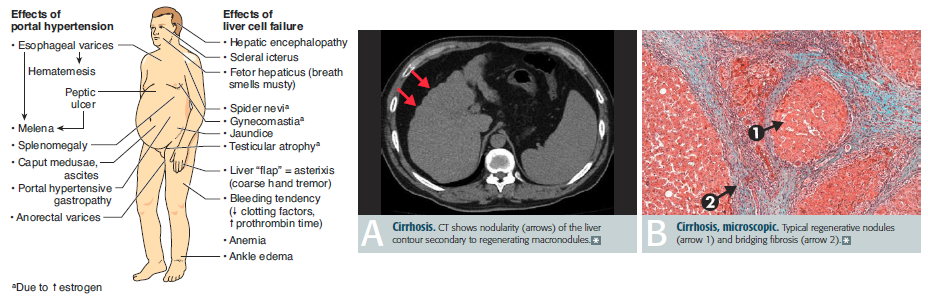

Cirrhosis and portal hypertension (360)